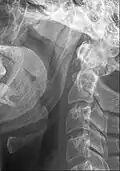

O ligamento estilo-hióideo normalmente contém uma pequena cartilagem no seu centro, que costuma ser parcialmente ossificada na síndrome de Eagle .[3]

O ligamento estilo-hióideo é um ligamento que se estende entre o osso hióide e o processo estiloide do osso temporal (osso temporal do crânio).

Fixa-se no corno menor na parte inferior do osso hióide,[1][2] e (o ápice do[1] ) o processo estilóide do osso temporal[1][2]superiormente.

O ligamento é adjacente à parede lateral da orofaringe .[1]

Inferiormente, é adjacente ao hioglosso .[1]